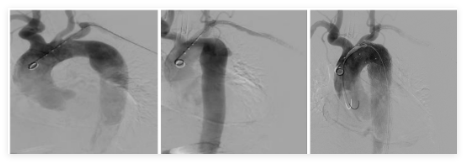

2.腹主动脉覆膜支架腔内隔绝术

①血管栓塞术:通过导管推入带纤毛弹簧圈,栓塞髂内动脉,防止内漏、出血等。

②血管内支架植入术:在扩张的动脉瘤内放置覆膜支架,隔绝异常瘤腔,防止破裂出血。

③血管扩张成形术:采用球囊扩张方式,使支架重叠处充分贴合,防止内漏发生。